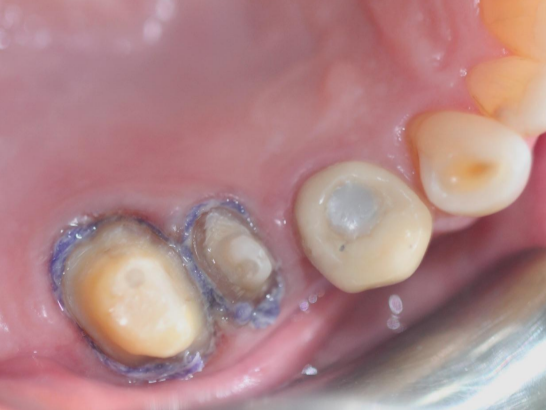

Step 4: Place the second retraction cord in the gingival sulcus

Choose a retraction cord that fills the gingival sulcus. It can be observed that the retraction cord completely surrounds the tooth. The second retraction cord often needs to be impregnated with hemostatic material.

Step 5: Remove the second retraction cord

Assess the bleeding situation, water control, and whether the complete shoulder edge line is visible.